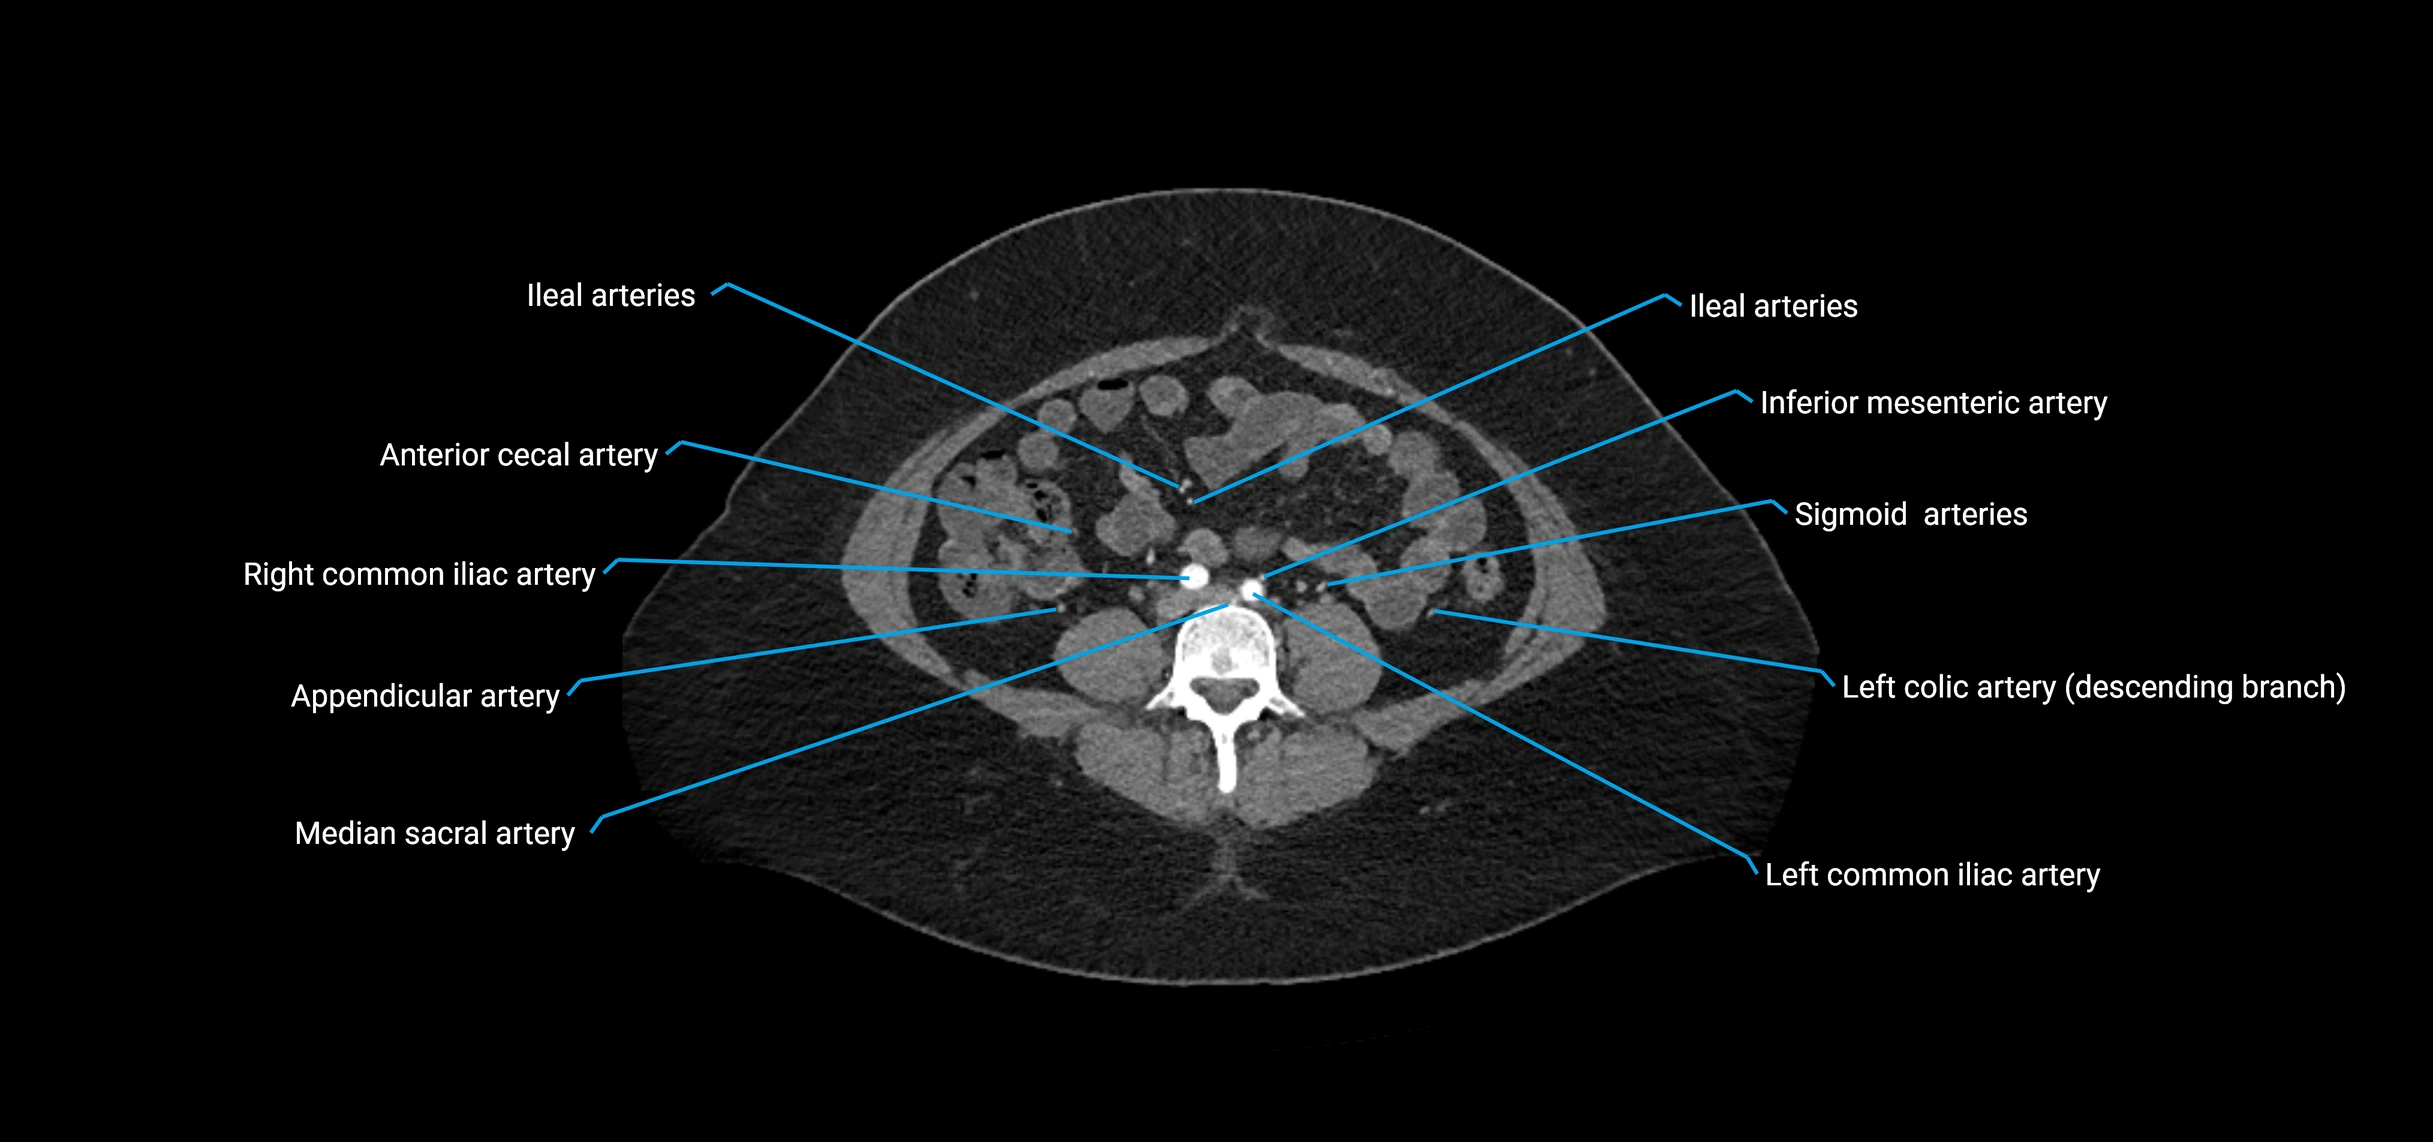

• Unpaired visceral branches: celiac trunk, superior mesenteric artery (SMA), inferior mesenteric artery (IMA)

• Terminal branches: right and left common iliac arteries

Contrast-enhanced CT (CTA):

• Gold standard for abdominal aortic imaging

• Provides excellent detail of lumen, wall, aneurysm, thrombus, and branch vessels

• Multiplanar and 3D reconstructions help in aneurysm measurement, stent graft planning, and dissection evaluation

• Detects acute rupture, traumatic injury, or occlusion with high sensitivity